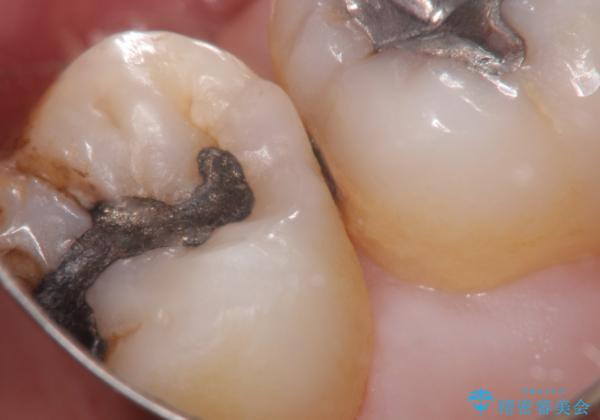

むし歯の治療。ゴールドインレーによる修復

- 定期健診にてむし歯を認めたためゴールドインレーにて治療を行いました。

拡大鏡で常に口腔内を診察しているため、小さなむし歯も見逃さずに治療を行っています。

ゴールドインレーは適合が良く、割れることもないため、長期的に安定した治療法となります。